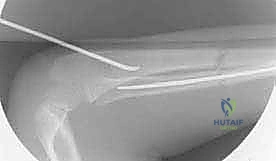

تُعد تقنية التثبيت بالمسامير المرنة داخل النخاع (Flexible Intramedullary Nailing - FIN) أو مسامير التيتانيوم المرنة (Titanium Elastic Nails - TENs) المعيار الذهبي (Gold Standard) لعلاج كسور الساعد غير المستقرة لدى الأطفال. والأستاذ الدكتور محمد هطيف هو رائد هذه التقنية في اليمن.

مبدأ عمل المسامير المرنة

على عكس الشرائح والمسامير التقليدية (Plates and Screws) التي تتطلب شقوقاً جراحية كبيرة وتؤدي إلى تقشير السمحاق (مما يضعف التروية الدموية للعظم)، تعمل المسامير المرنة بمبدأ مختلف تماماً.

يتم إدخال مسمارين مرنين (عادة من التيتانيوم أو الصلب الطبي المقاوم للصدأ) داخل التجويف النخاعي (Marrow Canal) للعظم. يتم ثني هذه المسامير مسبقاً بواسطة الجراح لتشكيل قوس. عندما يتم إدخالها في العظم، فإنها تعمل بمبدأ "التثبيت ثلاثي النقاط" (Three-Point Fixation). تولد المسامير المرنة قوة شد داخلية تدفع أجزاء العظم المكسور نحو بعضها البعض، مما يوفر استقراراً حيوياً ميكانيكياً (Biomechanically Stable) يسمح بتكوين الكالس (Callus) وشفاء العظم بسرعة فائقة.